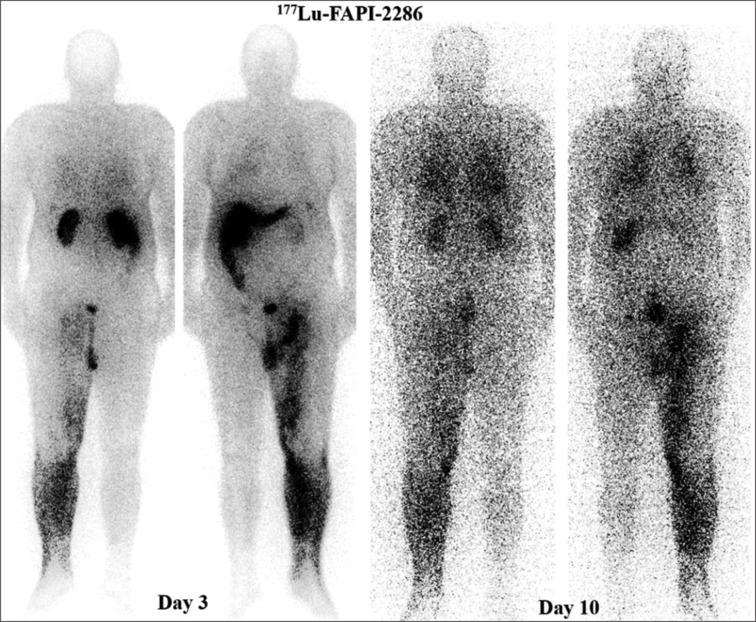

一位55岁男性晚期恶性黑色素瘤患者接受了手术、放疗和化疗。尽管进行了这些治疗,[18F]FDG PET/CT显示疾病进展明显。使用镓-68示踪剂对CXCR4、SSTR2和FAP进行靶向成像,确定了个性化治疗的生物标志物。这导致了[177Lu]Lu-FAPI-2286的选择。在第一个周期后,患者报告疼痛缓解,但随后的影像学显示快速脑转移。这个病例强调了个性化医疗和分子成像在治疗晚期黑色素瘤中的重要性。

A 55-year-old male with advanced malignant melanoma received surgery, radiotherapy, and chemotherapy. Despite these treatments, [18F]FDG PET/CT showed significant disease progression. Targeted imaging with gallium-68 radiotracers for CXCR4, SSTR2, and FAP identified biomarkers for personalized therapy. This led to the choice of [177Lu]Lu-FAPI-2286. After the first cycle, the patient reported pain relief, but subsequent imaging revealed rapid brain metastasis. This case highlights the importance of personalized medicine and molecular imaging in treating advanced melanoma.